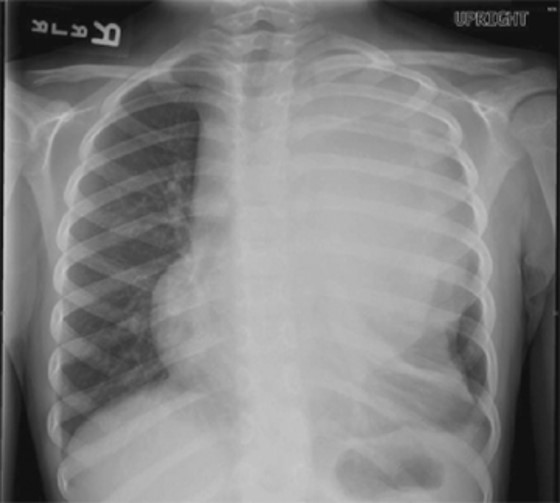

Chapter 11: Hematology and Oncology in Atlas of Pediatric Emergence Medicine, 3e, describes the physical symptoms of acute lymphoblastic leukemia. One such symptom is a mediastatal mass, as illustrated in Figure 40-1 (below).

Figure 40-1: Stone C, Humphries RL, Drigalla D, Stephan M. CURRENT Diagnosis & Treatment: Pediatric Emergency Medicine; 2014.